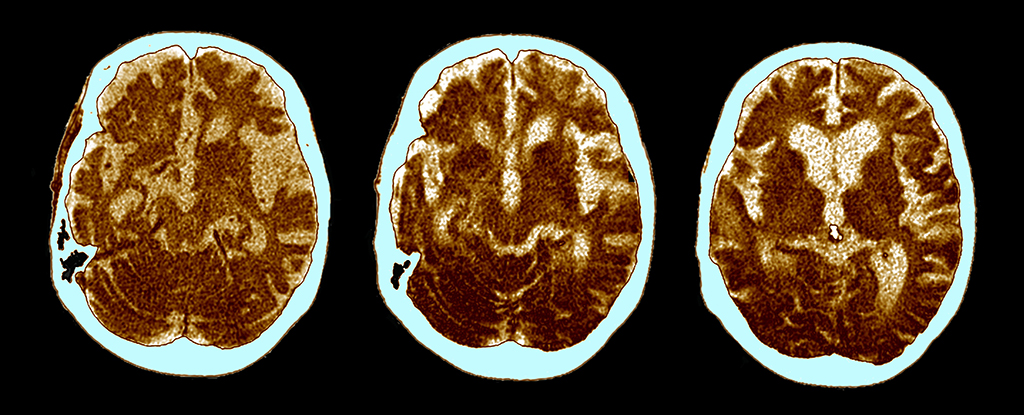

A Cedars-Sinai study finds Chlamydia pneumoniae in the retina—more abundant in people with Alzheimer's—where infection correlates with cognitive decline. Lab tests in neurons and animal models show infection-driven inflammation, neuron death, and amyloid-beta buildup, suggesting retinal infection could reflect brain pathology and serve as a noninvasive biomarker and potential treatment target, though causality is not proven.